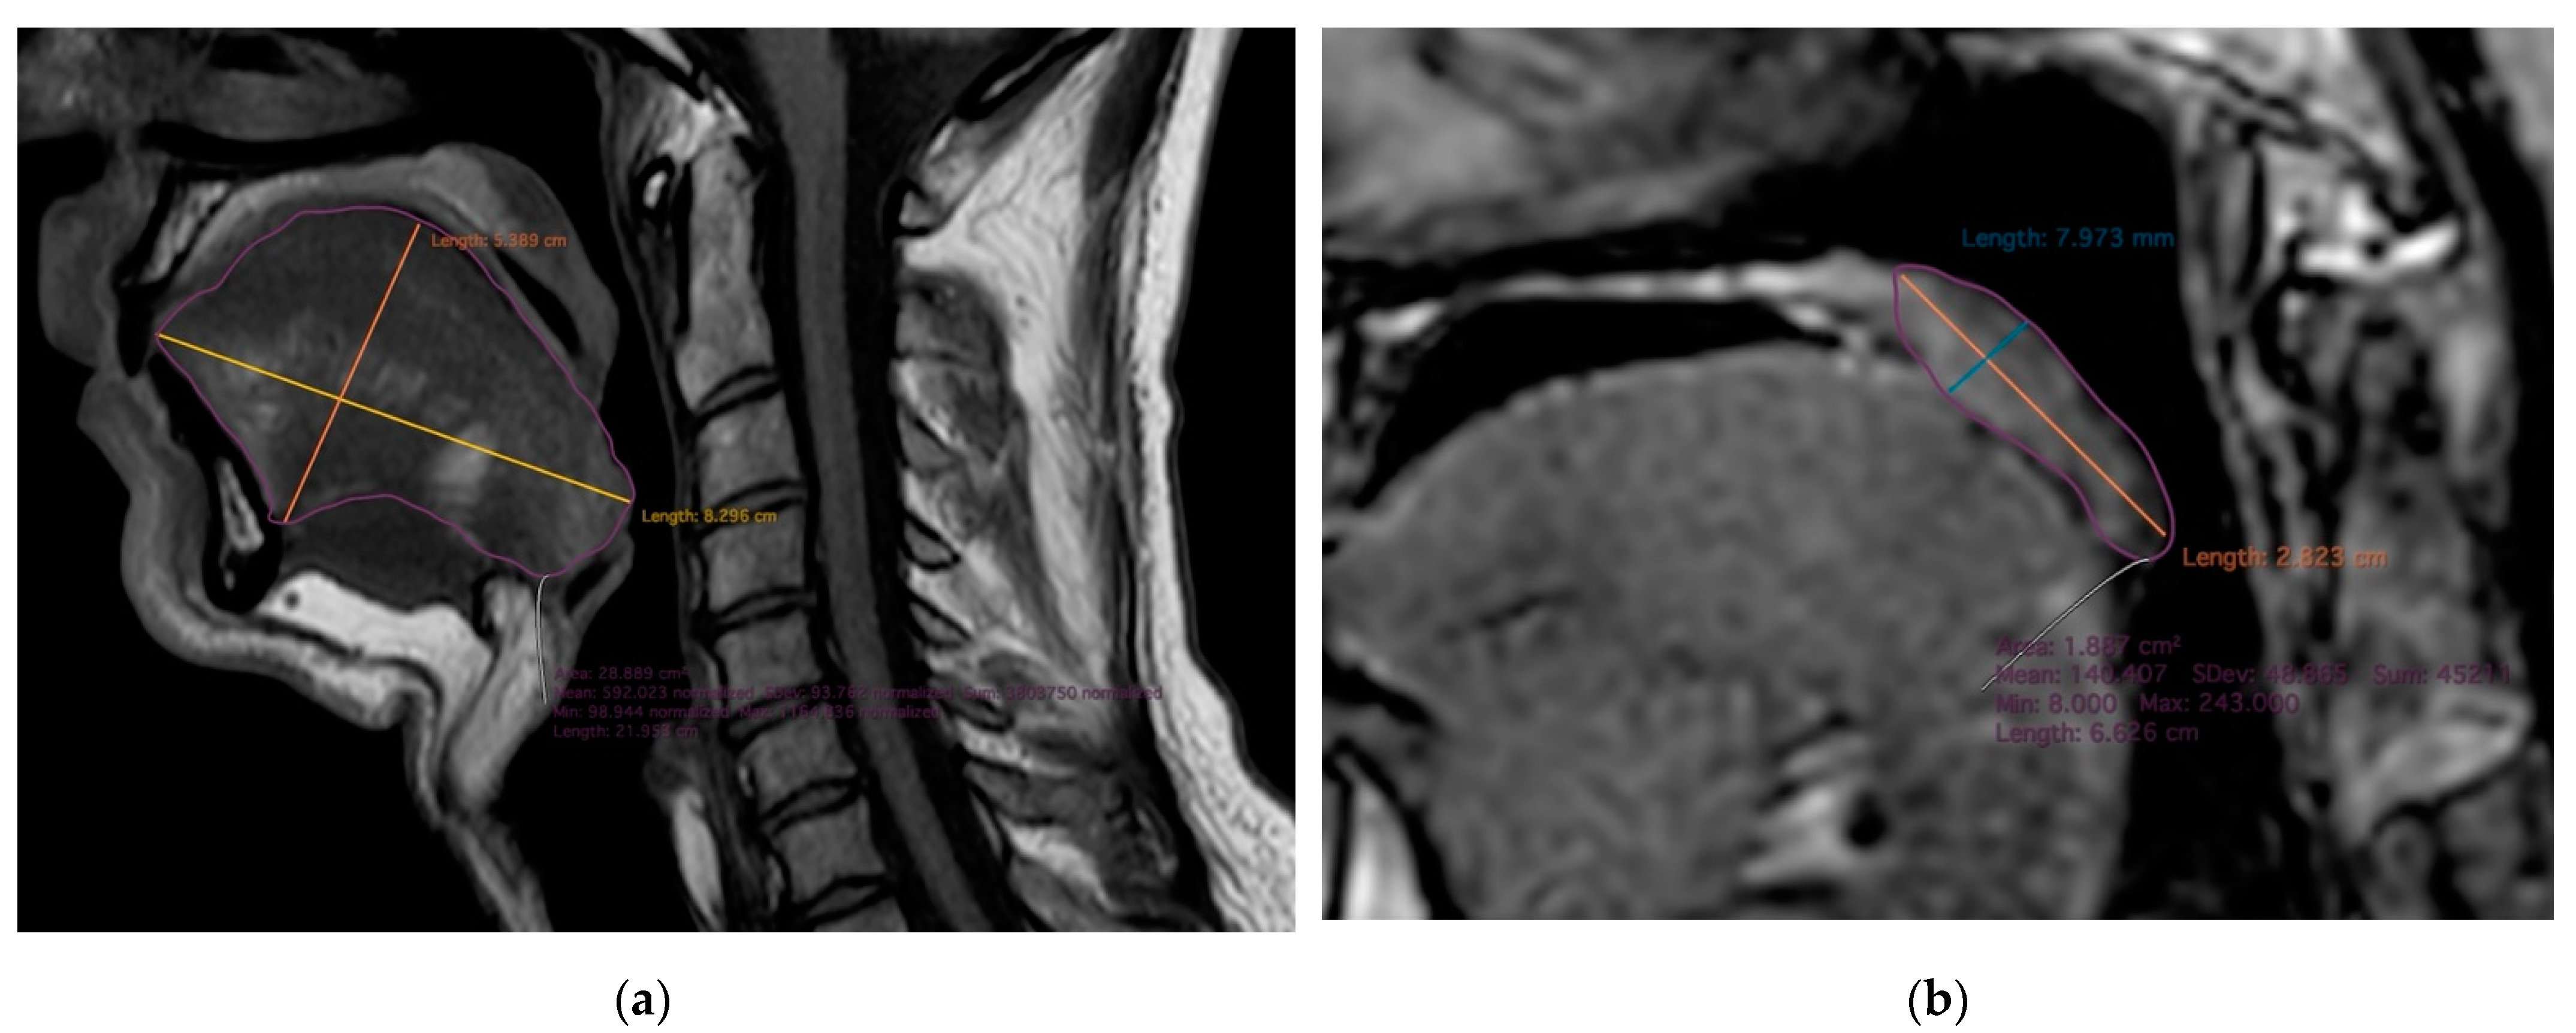

2.2. MR Imaging